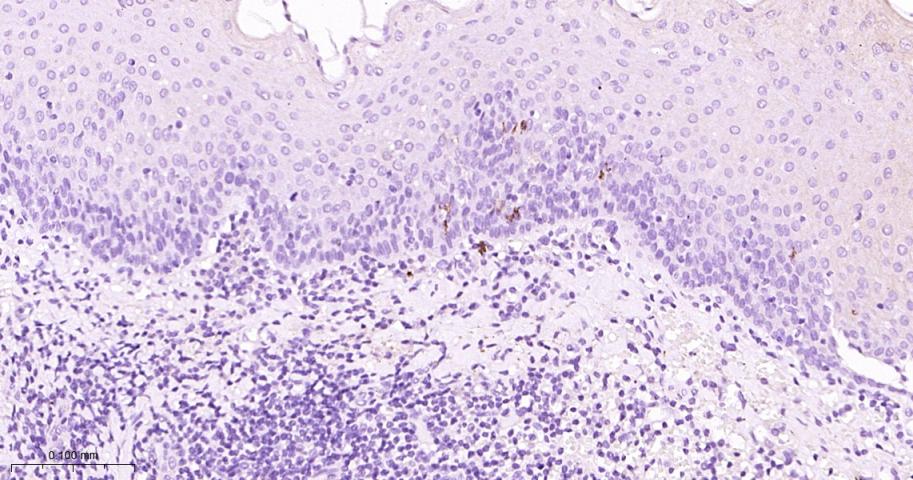

Paraformaldehyde-fixed, paraffin embedded Human Thymus; Antigen retrieval by boiling in sodium citrate buffer (pH6.0) for 15 min; Antibody incubation with CD1A Monoclonal Antibody, Unconjugated(bsm-60907R) at 1:200 overnight at 4°C, followed by conjugation to the bs-0295G-HRP and DAB (C-0010) staining.

Paraformaldehyde-fixed, paraffin embedded Human Tonsil; Antigen retrieval by boiling in sodium citrate buffer (pH6.0) for 15 min; Antibody incubation with CD1A Monoclonal Antibody, Unconjugated(bsm-60907R) at 1:200 overnight at 4°C, followed by conjugation to the bs-0295G-HRP and DAB (C-0010) staining.